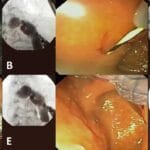

El balón gástrico es un procedimiento médico utilizado para perder peso. Consiste en la colocación de un globo de silicona en el estómago, que se llena con suero o aire para reducir la capacidad del mismo y generar una sensación de saciedad.

El balón gástrico es un tratamiento no quirúrgico utilizado para ayudar en la pérdida de peso. Consiste en la colocación de un globo inflable en el estómago, lo que provoca una sensación de saciedad y reduce el apetito.